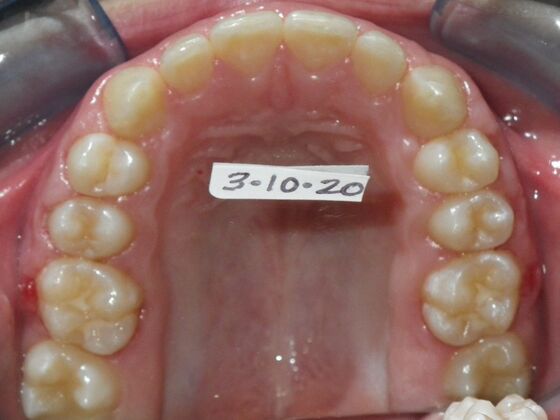

Dylan presented with a functional crossbite in which we used removable expansion appliances for 12 months, followed by bracketing of upper and lower teeth including primary ones to gain alittle more expansion, allowed to wear retainers for 6 months and then followed closely with 6 month ortho recalls and began Phase 2 treatment within 24 months and finished his ortho treatment.